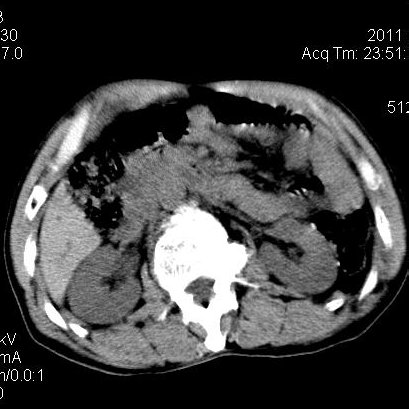

肝左叶发育异常

男性,55岁,骑摩托车摔倒后入院,自述右上腹疼痛

[backcolor=#FF0000]第一次诊断的时候也是这么肯定,可是床旁超声检查并没有发现明显异常,而且患者的一般症状都良好。还好临床只是保守治疗,没有立即手术,第二次复查的时候没有一点变化,又做了MRI检查,没有血肿,

这是一例肝左叶发育异常的,很个性吧~[/backcolor]